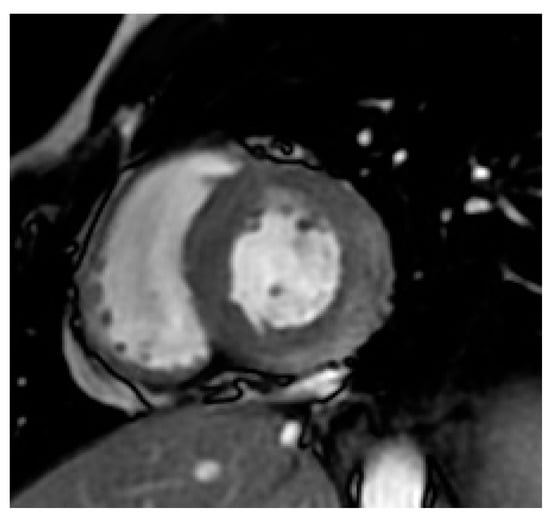

A 23-year-old male patient without past medical history presented to the emergency room with recent retrosternal chest tightness and pain. He reported recent gastro-intestinal (GI) symptoms of nausea, vomiting, 4-day watery diarrhea with transient episode of fever (38.7 °C). At admission, physical examination showed an impaired general status. He was afebrile (37.2 °C), respiratory rate 20 per min., cardiac assessment showed blood pressure of 140/70 mmHg, regular tachycardia of 100 beats per minute and normal cardiac murmur. Pulmonary examination showed a respiratory rate of 16 cycles per min, and auscultation was normal. He denied abdominal pain, and palpation showed no tenderness and no liver or spleen enlargement. He reported generalized myalgia but rheumatological evaluation did not show arthritis or productive myalgia. The electrocardiogram (ECG) showed left axis deviation with regular sinusal tachycardia. Routine laboratory showed leukocytosis 13 G/L (normal range < 10 G/L), neutrophilia 8.2 G/L (normal range 1.5–7 G/L) and lymphopenia 600/mm3 (normal range 1500 to 4000/mm3) on cell blood count, with elevated C-reactive protein of 130 mg/dL (normal range < 5 mg/dL), serum electrolytes, creatinine and liver enzymes within normal limits. Maximum Troponins and creatine kinase MB (CK-MB) were elevated to 678 ng/L (normal range < 14 ng/L) and 54 ng/mL (normal range < 7 ng/mL). The patient was admitted to the cardiac department for further workup. He was managed symptomatically with analgesics, anti-reflux and fluids. Transthoracic echocardiography (TTE) revealed a preserved ejection fraction (EF) of 55% with normal wall motions, no valvular dysfunction, normal pulmonary pressure and no pericardial effusion. His risk of coronary artery disease (CAD) was low; moreover, clinical, biological and echocardiographic presentation summed the hypothesis of an acute myocarditis. A large etiological workup, including repeated peripheral blood culture, Mycoplasma pneumoniae, Chlamydia pneumoniae, Coxiella burnetii, Borrelia burgdorferi, Leptospira spp., Rickettsia spp. and Brucella spp., was conducted. The serologies, such as urinary Legionella pneumophila antigen, were negative. Moreover, serologies of RNA viruses (coxsackieviruses A and B, hepatitis C virus, human immunodeficiency virus) and DNA viruses (adenoviruses, parvovirus B19, cytomegalovirus, human herpes virus-6, Epstein-Barr virus, varicella-zoster virus and herpes simplex virus) were negative. Autoimmune assessment, including antinuclear, anti-neutrophil cytoplasmic antibodies, systemic sclerosis and autoimmune myopathies specific antibodies and converting enzyme assay, were negative. The patient denied any recent drug intake. A Gram stain of specimen stool collected showed multiple curved and spiral Gram-negative rods. Biochemical tests indicated an oxidase, catalase and hippurate negative and indoxyl acetate-positive bacterial species, corresponding to C. jejuni. Stool cultures confirmed the diagnosis of C. jejuni sensitive to macrolides (Azithromycin/Roxithromycin/Clarythromycin) and flouroquinolones (Ciprofloxacin). Continuous telemetry monitoring showed some runs of non-sustained ventricular tachycardia (NSVT). Oral bisoprolol 2.5 mg twice daily was started for that, and oral 1 g of Azithromycin was administered. He remained clinically stable over the rest of the hospital course, and the diarrhea was progressively resolved. The patient remained stable, and we could perform cardiovascular magnetic resonance (CMR) imaging. Triple inversion-recovery black-blood T2-weighted STIR sequences showed focal areas of hypersignal in the subepicardium of the posterolateral left ventricular (LV) wall, indicative of myocardial edema (Figure 1). In addition, steady-state-free-precession (SSFP) cine CMR showed early hypersignal in the subepicardium of the posterolateral LV wall immediately after injection of 0.1 mM of Gadolinium chelates, indicating focal hyperemia (Figure 2). Inversion-recovery gradient-echo-based late Gadolinium enhancement techniques, acquired 10 min. after Gadolinium injection, revealed subepicardial nodular lesions of myocardial damage (Figure 3). The final diagnosis of C. jejuni-related acute myocarditis was supported by the Lake Louise criteria [7]. The patient was discharged free of symptoms after one week in hospital. On close follow-up, his C-reactive protein and cardiac enzymes normalized after three weeks. Repeated TTE and 24-h ECG were normal, so bisoprolol was progressively discontinued after 6 months. Control CMR imaging at 3 months showed regression of the focal areas of hyper signal in the sub epicardium of the posterolateral left ventricular (LV) wall.

Figure 3. Inversion-recovery gradient-echo-based late Gadolinium enhancement images, acquired 10 min. after Gadolinium injection, showing subepicardial nodular lesions of myocardial damage (arrows).